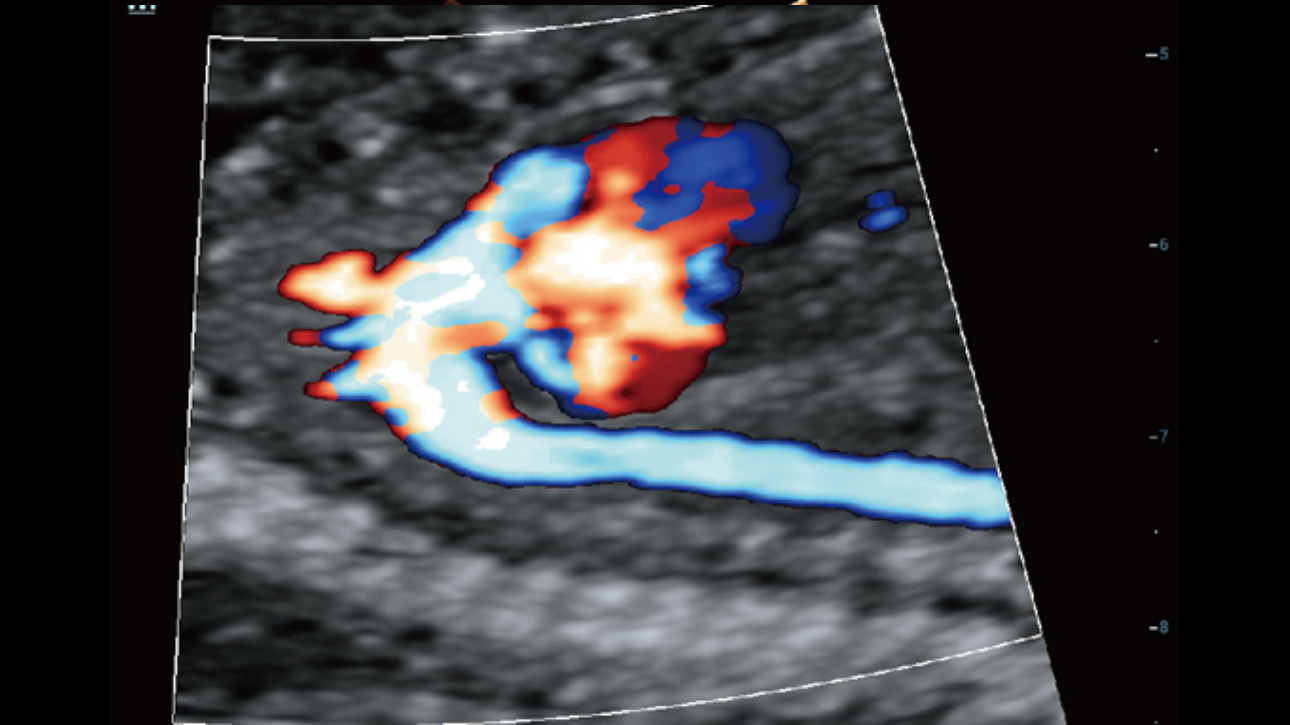

The channel data based ZST+ is an extraordinary innovation, representing an ultrasound evolution. Transforming ultrasound metrics from conventional beamforming to channel data based processing; ZST+ is able to deliver multiple imaging advances: Advanced Acoustic Acquisition, Dynamic Pixel Focusing, Sound Speed Compensation, Enhanced Channel Data Processing and Total Recall Imaging.

By transmitting and receiving a relatively smaller number of large zones, Advanced Acoustic Acquisition extracts more information from each acquisition, 10 times faster than a conventional line-by-line beamforming method.

Channel data based ZST+ provides Enhanced Channel Data Processing for greatly improved imaging clarity. By multiple and retrospective channel data processing, it makes the best use of acoustic information for image improvement.